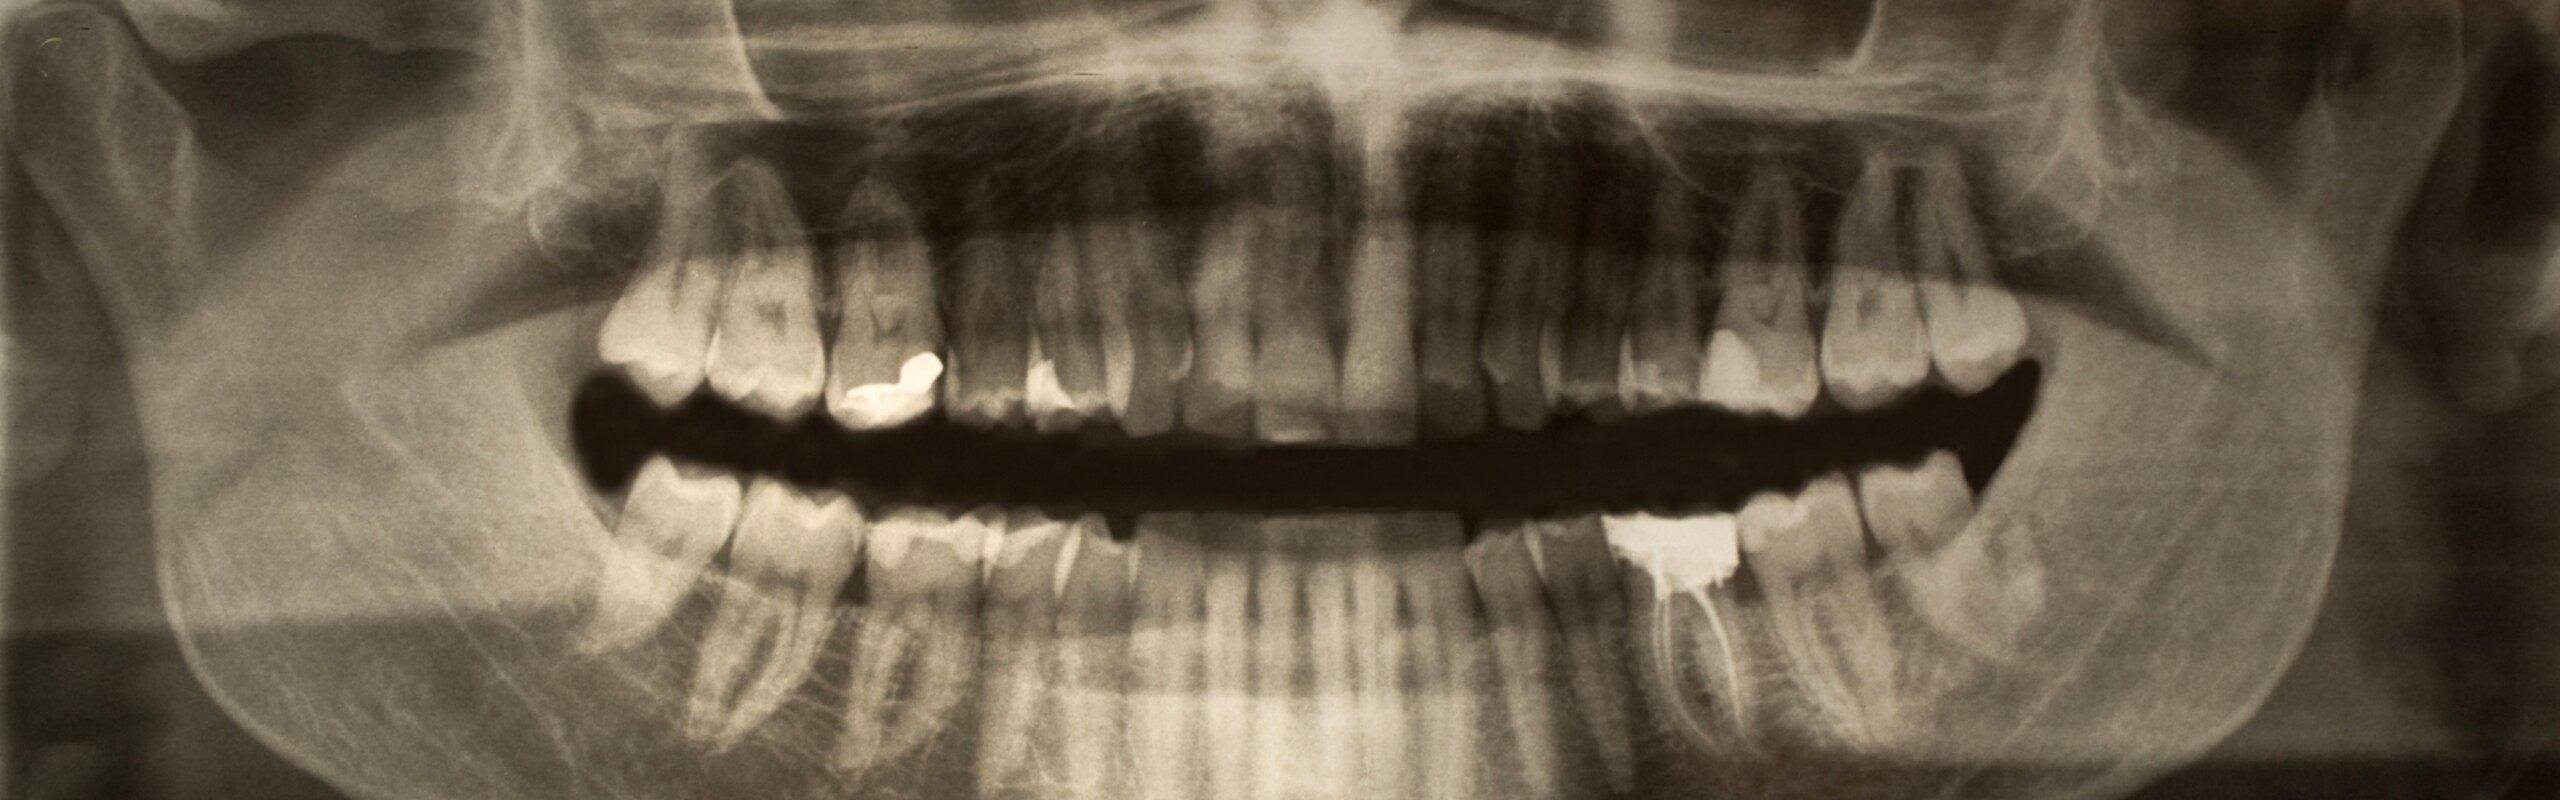

Forskargrupp Vår grupp studerar mekanismer hos bakterien A. actinomycetemcomitans i samband med parodontala sjukdomar.

Parodontala sjukdomar är bland de vanligaste kroniska infektionerna i världen, och snabb tandfästeförlust hos unga individer (<35 år) är starkt förknippad med infektion av bakterien A. actinomycetemcomitans. Dess speciella egenskaper är mest avgörande i de inledande skedena av tandlossningsprocessen. Produktion av leukotoxin hos bakterien är kopplat till hög virulens, men vi vet inte varför även låg-leukotoxiska isolat av bakterien kan vara högvirulenta. Bakterien kan också bidra till systemiska sjukdomar som hjärt- och kärlsjukdom, och reumatoid artrit orsakad av hypercitrullinering.

Jan Oscarsson lab använder cell- och molekylärbiologiska metoder för att studera mekanismer hur A. actinomycetemcomitans kan orsaka skador och överleva inom värden. Vi vill till exempel förstå hur denna organism frigör inflammatoriska substanser som kan trigga parodontal inflammation. Vi har identifierat mekanismer för hur bakteriens frisläppta membranvesiklar (membranblåsor) kan interagera med värdceller, orsaka patogena effekter, fungera som transportverktyg för specifika effektormolekyler, samt bidra till bakteriell serumresistens. Vi har visat att bakterien kan överleva i humanserum tack vare membranproteinerna OmpA1 och OmpA2, och att H-NS, ett regleringsprotein hos bakterien, styr dess förmåga att bilda biofilm och dess interaktioner med andra orala bakteriearter i biofilmmodeller.

Genom att lära oss mer om virulensmekanismer hos A. actinomycetemcomitans hoppas vi kunna bidra till nya sätt att avväpna bakteriens virulens snarare än att döda den. På grund av en stor genetisk variation inom arten tycks vissa stammar av bakterien vara mer förknippade med virulens. Vi använder bland annat helgenomsekvensering för att identifiera genetiska markörer som kan användas för att identifiera högvirulenta genotyper av denna bakterie. Genom att använda oss av data från en tidigare insamlad patientkohort i Ghana har vi identifierat en genotyp, cagE, som är förknippad med hög leukotoxinproduktion och progress av tandfästeförlust. Hos patienter som kommer hit för parodontal behandling är denna genotyp är ungefär tio gånger vanligare än den redan kända högleukotoxiska genotypen JP2, och finns hos en hög andel av de patienter som är under 35 år. Sådana markörer skulle kunna användas som ett diagnostiskt och prognostiskt verktyg för preklinisk identifiering av individer med hög risk för en aggressiv form av parodontit, och för att underlätta spårning av hur högvirulenta varianter sprids.